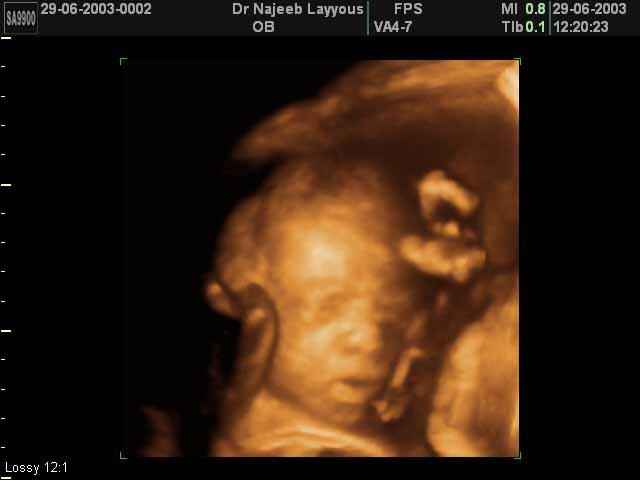

3D Fetal Face Ultrasound Scan Photos